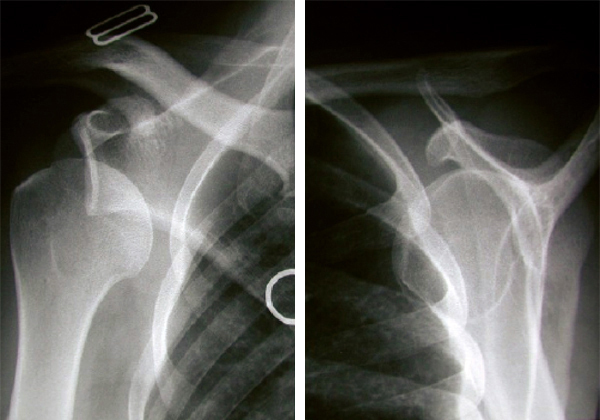

Luxation gléno-humérale antéro-inférieure

2. Luxation gléno-humérale antéro-inférieure